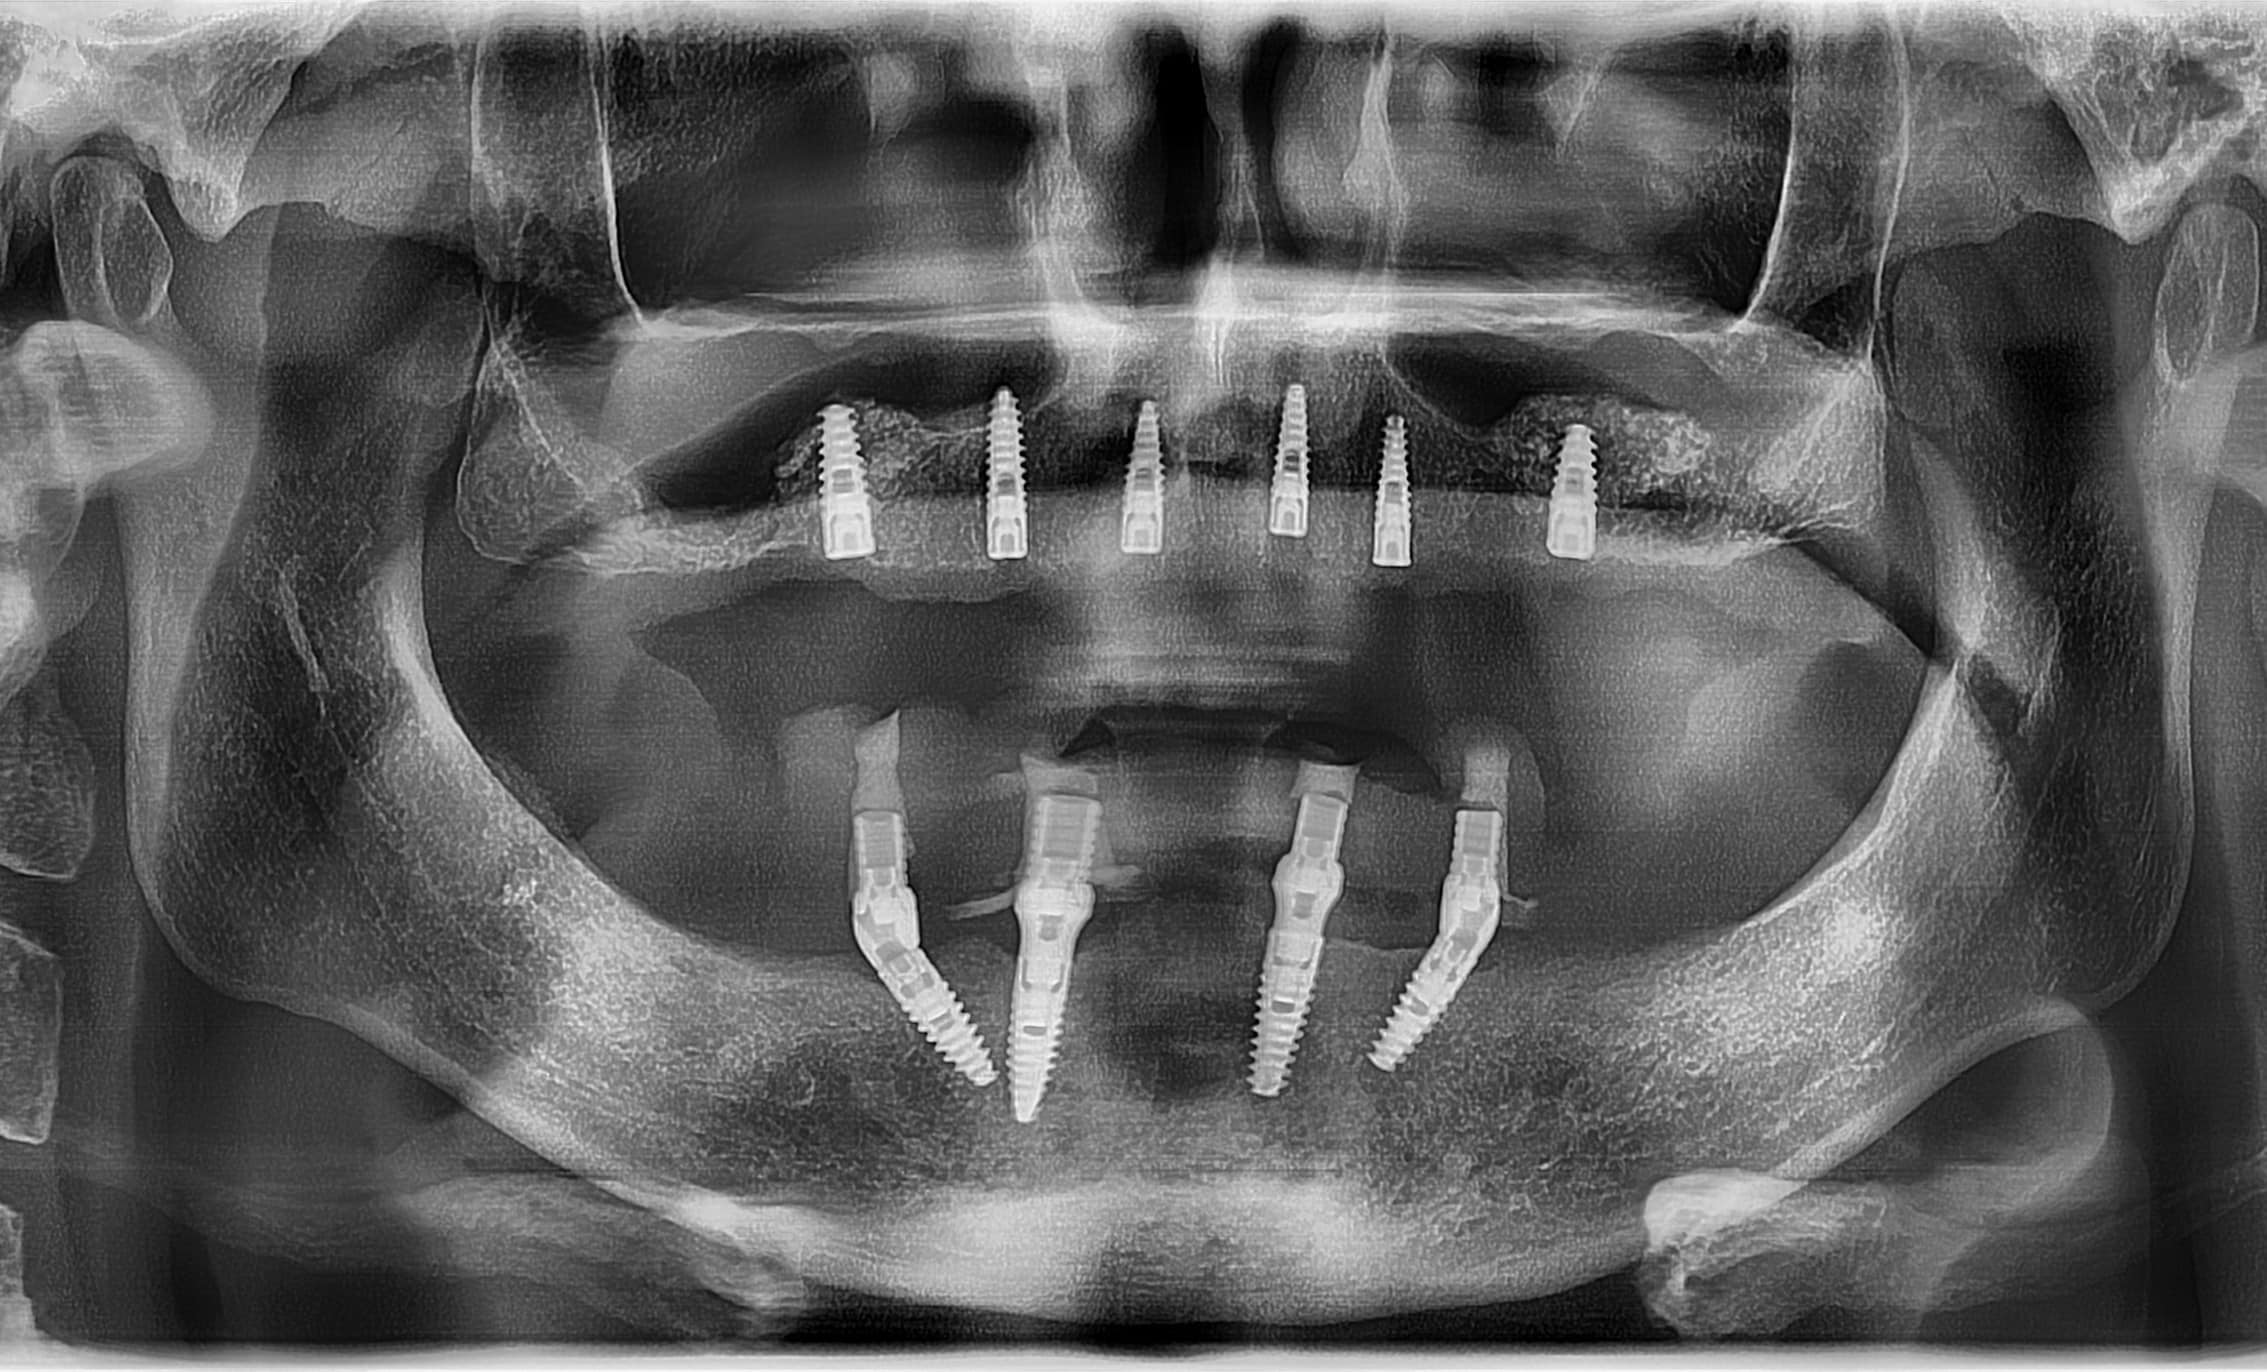

După o perioada de 6 luni, a demarat cea de a doua etapă a planului de tratament. Aceasta a constat în realizarea unui lifting sinus maxilar bilateral și inserarea a 6 implanturi cu ajutorul ghidului chirurgical DigiRay.

Această variantă de tratament a fost aleasă datorită volumului osos redus și a densității osoase scăzute din regiunea frontală maxilară.

În cazul de față, ca și lucrare protetică au fost alese coroanele pe implant. Datorită densității osoase reduse, nu s-a putut realiza încarcarea imediată a implanturilor.

Pentru a asigura stabilitatea ghidului chirurgical pe câmpul protetic, șablonul chirurgical a fostfixat cu ajutorul celor 3 pini de stabilizare plasați în zona posterioară și în zona frontală.